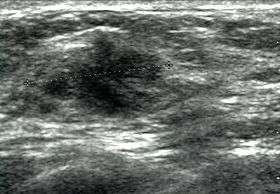

Breast ultrasound is the use of medical ultrasonography to perform imaging of the breast.

It can be considered either a diagnostic or a screening procedure.[1]

It may be used either with or without a mammogram.[2]

It may be useful in younger women, where the denser fibrous tissue of the breast may make mammograms more difficult to interpret.[3]